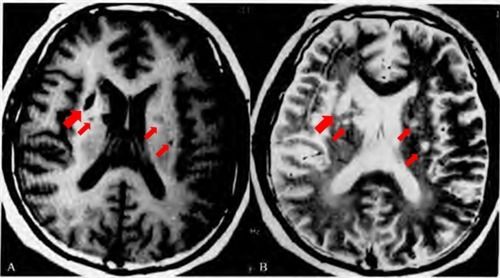

汇总| 超早期脑梗死ct征象

脑梗死丨演变,血供区域分布,ct表现

夜班不求人急性脑梗死的ct诊断

手把手教程:脑梗死影像读片入门

脑梗塞ct诊断

脑梗死CT

磁共振脑梗死图片

脑梗死ct影像表现图片

ct脑梗死图片讲解

脑梗死ct影像图片

脑梗死图片解析

脑梗死核磁

脑梗死ct图片